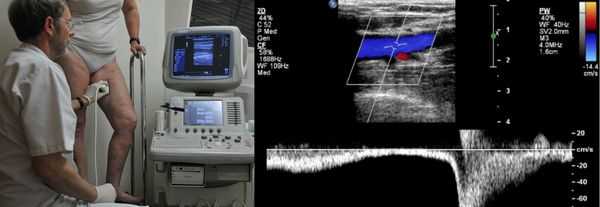

Проведение диагностики ХВН на ранних стадиях способствует ускорению лечения. При диагностике важно определить стадию заболевания. После общего клинического осмотра врач проводит дуплексное ангиосканирование вен нижних конечностей, чтобы определить тактику лечения. Дуплексное ангиосканирование поможет оценить состояние исследуемых сосудов, увидеть места их сужений или расширений, а также выявить тромбообразования.

Одним из самых доступных методов диагностики данного заболевания является УЗИ, главным преимуществом которого является многоразовость применения без рисков для здоровья, безболезненность, а также возможность выявить нарушения в текущей работе венозного аппарата. [3]

Для получения лучшего результата обследование рекомендуется проводить во второй половине дня. Поскольку именно после дневной нагрузки на ноги можно провести более точную оценку состояния клапанов, диаметра вен и степени поражённости стенок. На тактику лечения влияет наличие тромба в просвете вен, который приводит к нарушению тока крови и несёт наибольшую угрозу для жизни пациента.

Основной и самый доступный метод инструментальной диагностики — это ультразвуковое дуплексное сканирование вен нижних конечностей (УЗДС) [6] .

Ультразвуковая диагностика варикоза вен нижних конечностей

Золотым стандартом считается дуплексное ангиосканирование. Этот метод сочетает в себе ультразвуковое исследование и доплеровское сканирование. Таким образом, можно в режиме реального времени увидеть состояние сосудистой стенки и оценить скорость кровотока в венозной системе нижних конечностей.